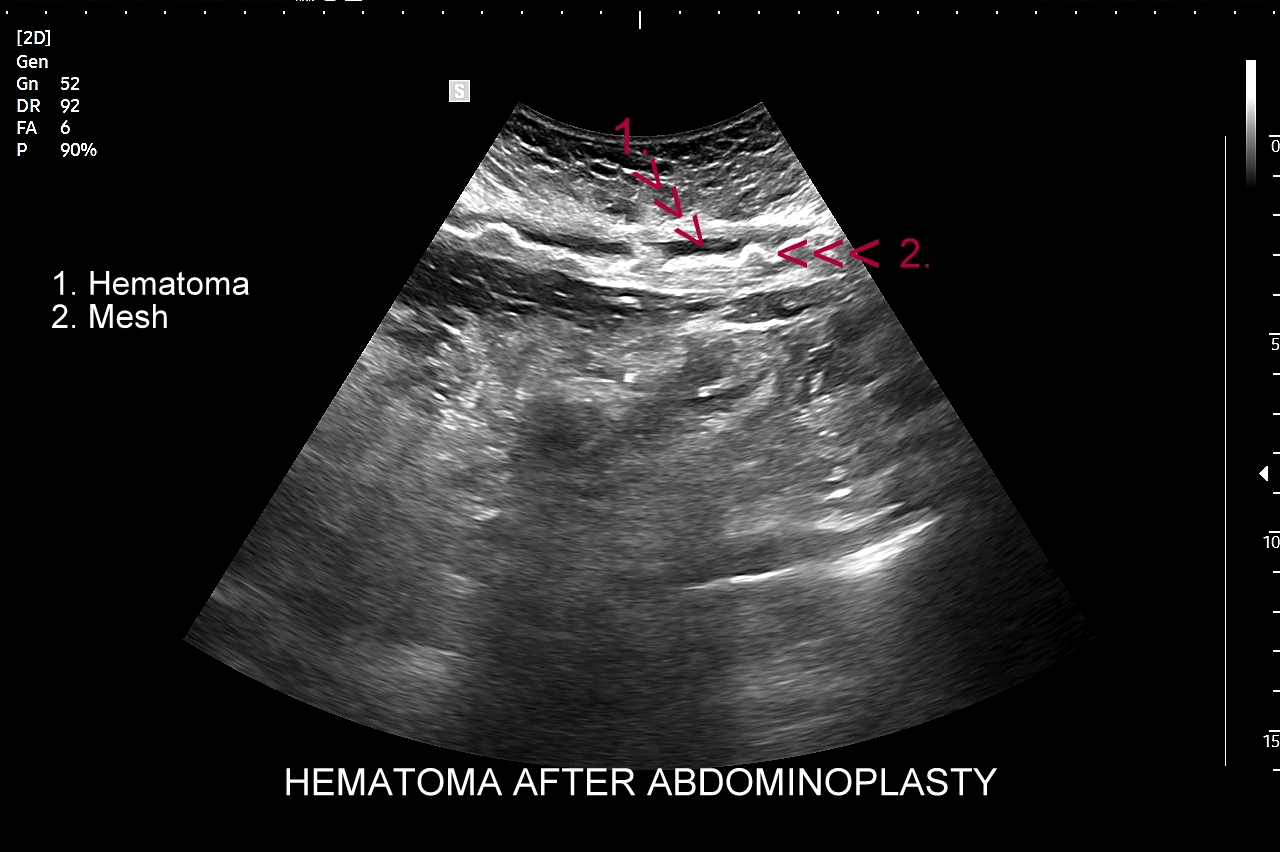

W prezentowanym przypadku zobaczyć można krwiaka w powłokach brzucha po operacji abdominoplastyki, który lokalizuje się pomiędzy tkanką podskórną a powięzią i siatką wzmacniającą; widać również kanał po jego drenażu.

Czym różni się krwiak od ropnia? Ich optymalne różnicowanie należy oprzeć na całości danych medycznych. W obrazowaniu USG krwiak w postaci zbiornika krwi początkowo jest bezechowy lub głęboko hypoechogenny; w miarę dojrzewania wypełnia się echogennym włóknikiem w postaci coraz to mocniej odbijających i ostrych ech; końcowym etapem krwiaka jest jego hyperechogenne i ograniczone do pierwotnego obszaru zwłóknienie. W przypadku ropnia jego granice są zatarte, dochodzi do widocznego w obrazowaniu Dopplerowskim przekrwienia zapalnego na granicy ropnia i tkanek otaczających; w samym zbiorniku ropnym gromadzi się gęsty, nieregularny i płynny materiał o typie debris. W różnicowaniu krwiaka i ropnia bierze się również pod uwagę badanie podmiotowe, przedmiotowe oraz laboratoryjne parametry zapalne w postaci WBC, CRP.